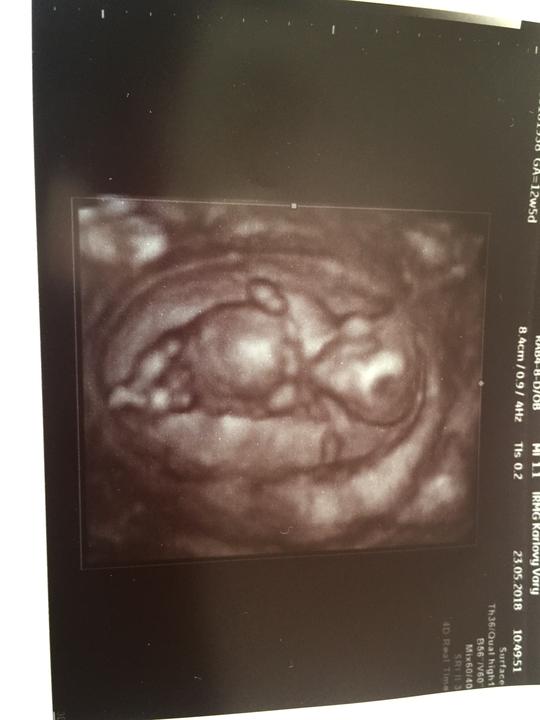

Dneska ve 12tydnu 😻👣🍼 snad to nejhorší máme už za sebou 😊😻

Už se nemůžu dočkat 23.5 jedeme na 3D ultrazvuk a tam nám řeknou co to bude buď Holcicka a nebo chlapeček 🍼👣😍💋❤️